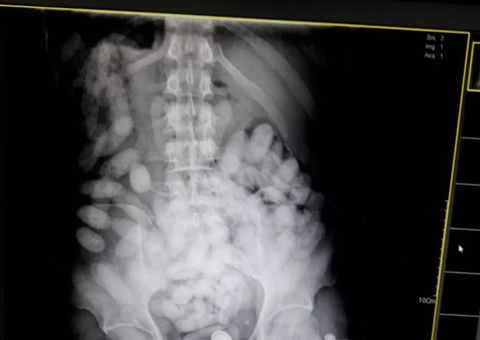

A vítima, que trabalha no Hospital 28 de Agosto como médico intensivista, sofreu múltiplos ferimentos pelo corpo e passa por uma cirurgia na unidade para remover o projétil da região torácica.